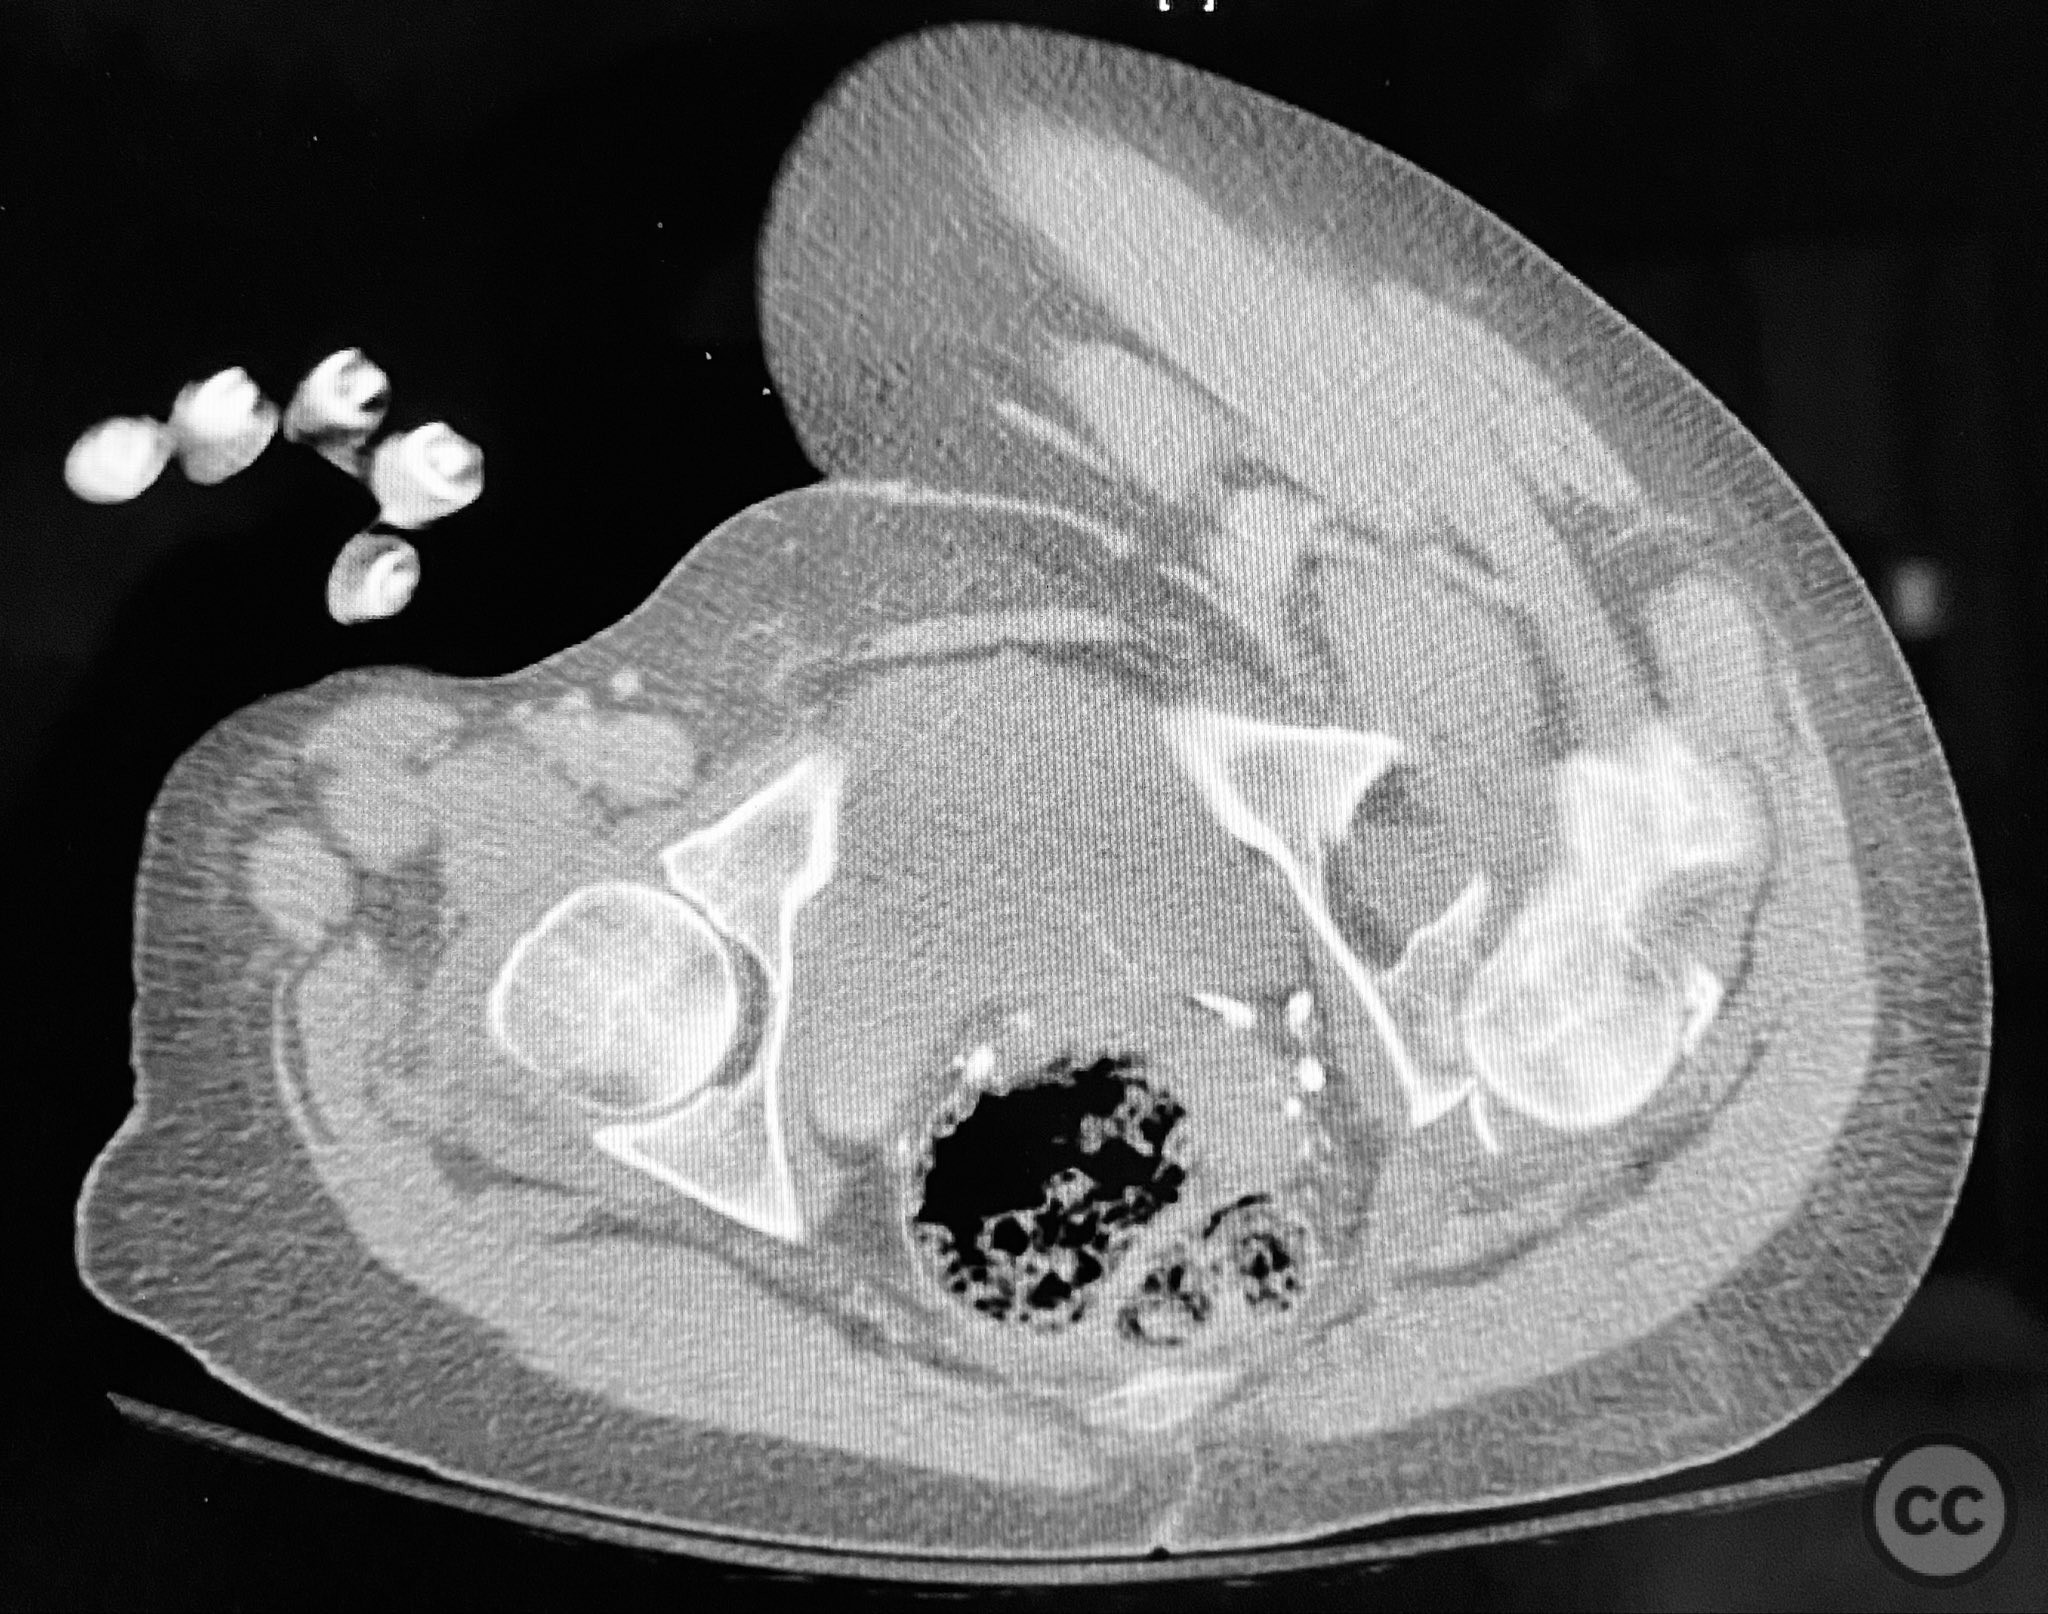

Clinical and radiological findings:  A patient sustained a posterior wall acetabular fracture-dislocation, characterized by comminution of the posterior wall, impaction of fragments into the posterior column region, and intra-articular loose fragments within the fossa acetabuli. Sagittal imaging demonstrated femoral head impalement on the intact wall, raising concern for potential irreducibility. Coronal and axial CT images revealed acetabular and femoral head impactions, peripheral wall comminution, incomplete fracture extension at the acetabular notch and quadrilateral surface, and an articular fragment within the joint. Surface renderings confirmed the extent of peripheral wall comminution and impaction. Despite these findings, a closed manipulative reduction was successfully achieved, resulting in a congruent reduction on post-reduction imaging.

Planning remarks:  The preoperative plan included a prone Kocher-Langenbeck (KL) approach to the acetabulum. The plan involved application of a distractor to facilitate removal of intra-articular loose fragments, elevation of impacted articular segments, bone grafting of resultant defects with ground allograft, and stabilization of the posterior wall with multiple plates, including a custom spring hook plate for peripheral fragment support.